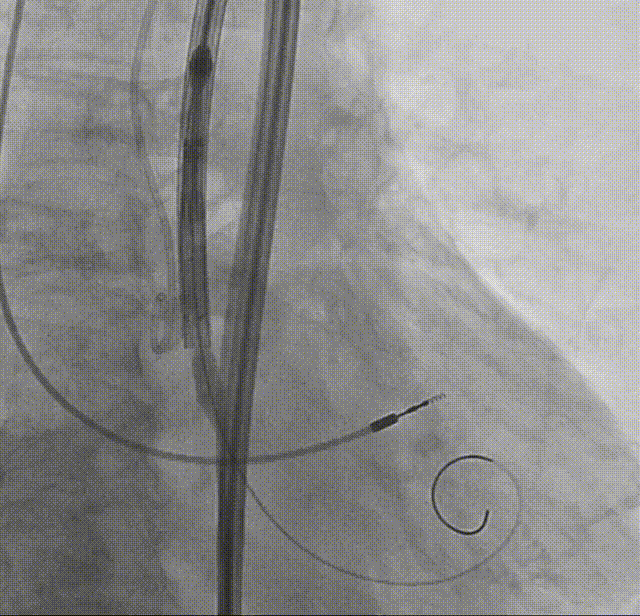

外周造影评估

术后超声

TAVR术后床旁超声描述:主动脉瓣位生物瓣位置、形态、回声、活动正常,生物瓣功能良好,主动脉瓣峰值跨瓣压差从术前126mmHg降至7mmHg,平均跨瓣压差从术前75mmHg降至3mmHg。心功能明显改善,LVEF恢复至73%,左室壁运动正常。